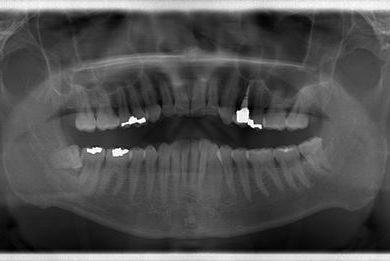

セラミック治療+歯肉歯槽骨整形術

| 性別/年齢 | 男性 / 45歳 | ||||||||||||||||||||||||||||||||

| 主訴 | 詰め物をしている歯が割れてしまったので、治療して欲しい。 | ||||||||||||||||||||||||||||||||

| 治療方針 | セラミック治療にて、審美的回復を行う。 | ||||||||||||||||||||||||||||||||

| 治療内容 | メタルボンドセラミッククラウン1本(メタルボンドセラミック用土台1本)、歯肉歯槽骨整形手術 | ||||||||||||||||||||||||||||||||

| 総治療費 | 157,185円 | ||||||||||||||||||||||||||||||||

| 治療期間 | 7ヶ月 |